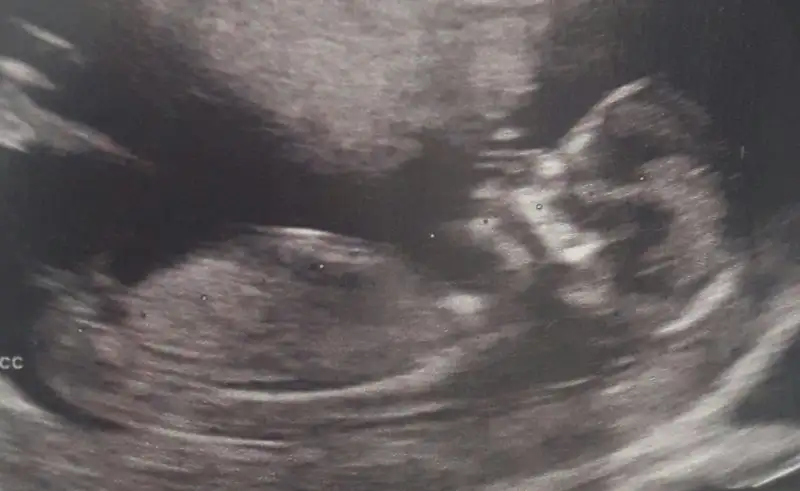

Kızlar öğrendik cinsiyetini bebeğimizin erkekmiş eşim kazandı ama doktor hiç düşünmeden söyledi kocaman boylu poslu bi erkek dedi çok mutluyum